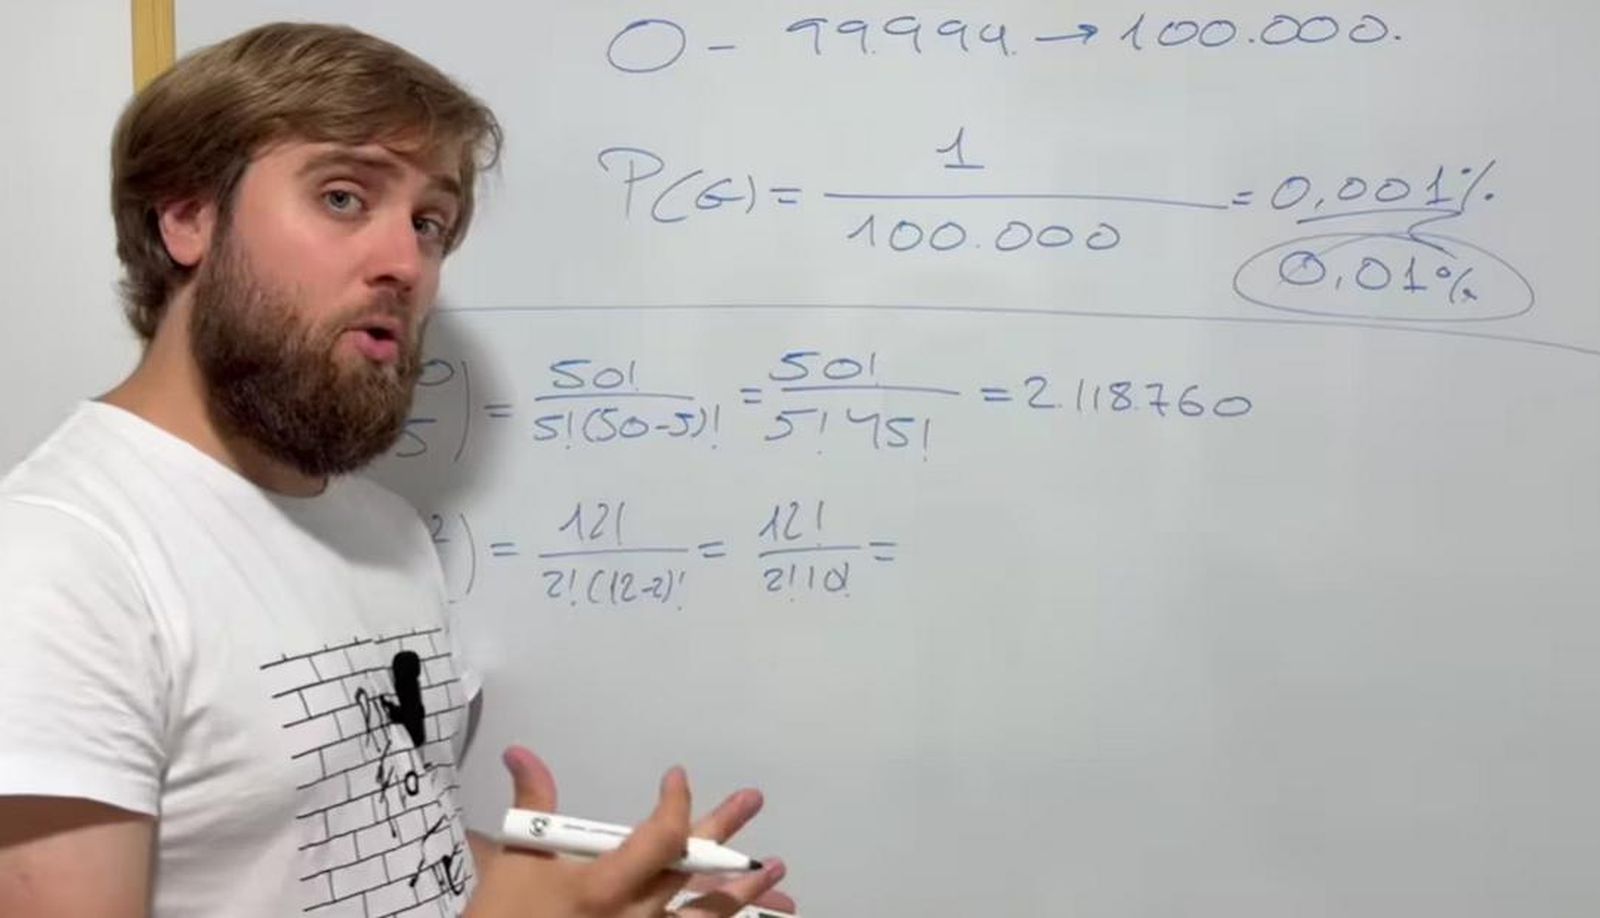

Determinar el origen de un tumor es clave para definir el pronóstico y el tratamiento más adecuado de un paciente. Cuando no se puede identificar el tumor primario, el diagnóstico puede complicarse. Un equipo de científicos de EE. UU. ha identificado una firma de ADN microbiano en el plasma sanguíneo capaz de distinguir entre cáncer de hígado primario y cáncer colorrectal metastásico con una precisión del 90%.

El estudio analizó ADN libre de células (cfDNA) en 16 pacientes con cáncer de hígado primario y 11 con cáncer colorrectal metastásico. El clasificador microbiano logró diferenciar ambos tipos de cáncer sin recurrir a inteligencia artificial, solo utilizando los fragmentos de ADN detectados en la sangre.

Según Amir Zarrinpar, profesor de Gastroenterología y Hepatología de la UC San Diego, “el uso de firmas de ADN microbiano podría abrir nuevas vías de diagnóstico, especialmente cuando las imágenes radiográficas no son concluyentes o no están disponibles”.